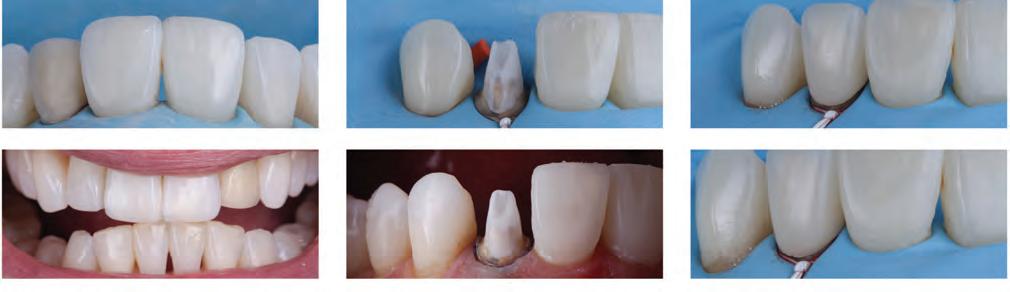

Fig. 1a: STL of maxilla arch. Fig. 1b: Digital wax-up will facilitate the planning phase.

Fig. 2a: Patient was concerned about the discoloration on the two upper central incisors.

Fig. 2b: Old restorations were removed, and the surface was air-abraded with 50-micron aluminum oxide.

Fig. 2c: Freehand technique used to close the diastema.

Fig. 2d: The final result is at the one-year recall.

Fig. 5a: The patient was unhappy about the appearance of her smile due to a Bolton discrepancy. Patient desires to have a beautiful smile.

Fig. 5b: Use palatal matrix with the proposed changes transferred from the wax-up.

Fig. 5c: Palatal contours built over the palatal matrix.

Fig. 5d: Post-operative results after restoration.

Fig. 6a: Patient requested to build peg laterals to fill the spaces between her teeth.

Fig. 6b: Clear PVS index try-in.

Fig. 6c: Injection of flowable composite.

Fig. 6d: Post-operative result.